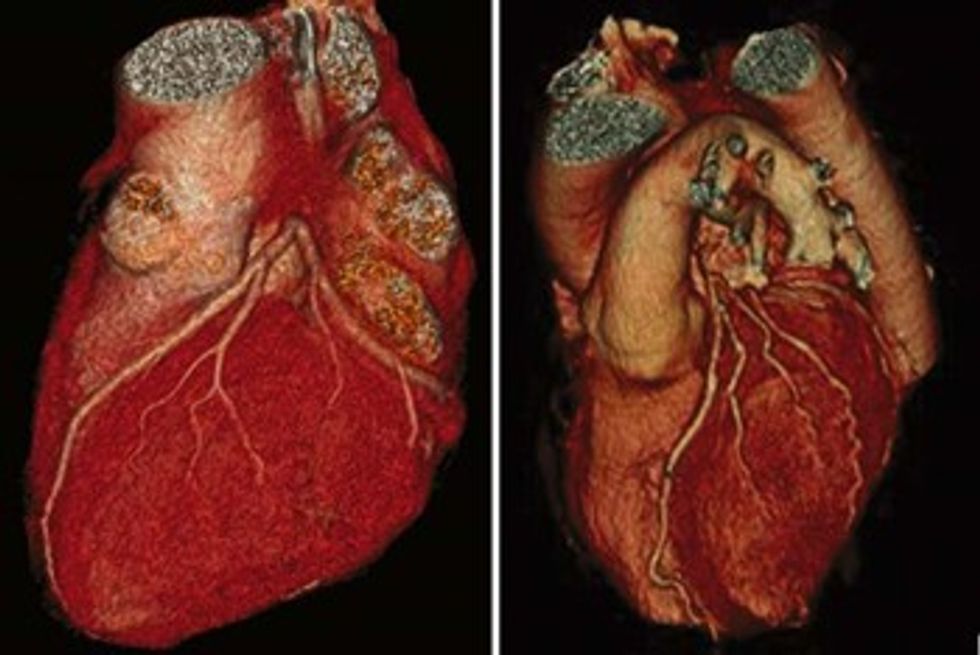

Me këtë, radiologjia bashkëkohore me koronarografi të realizuar me tomografi të kompjuterizuar mundëson vizalizimin e qartë të zemrës në tërësi dhe në raport me organet përreth.

Me koronarografi me tomografi të kompjuterizuar mund ta shohim zemrën në tërësi nga të gjitha anët, ku shohim muret e saj të formuara nga muskuli i zemrës dhe arteriet koronare në sipërfaqe.

Me koronarografi me tomografi të kompjuterizuar mund të bëjmë vlerësimin e rrezikshmërisë nga sëmundjet aterosklerotike duke vlerësuar vlerat e kalciumit të deponuar në enët e gjakut (Calcium scoring) ose ngushtimet e vet arterieve koronare (stenozave).

Me programe të posaçme softverike mund të bëhet rekonstruimi edhe i valvulës së aortës e cila del nga zemra.